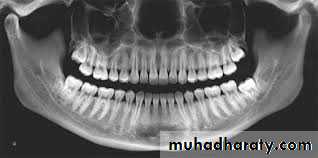

Periapical radiograph offers the highest definition and it should be used whenever possible, but the film should be positioned with care.

Orthopantomogram (OPG) is regarded as the radiograph of choice, its main advantages are; the low radiation exposure and its ability to demonstrate the entire dental arch.

Occlusal films are used in difficult cases especially in unerupted teeth in conjunction with another view at right angle, this is necessary to understand the problem in 3 dimensions.

Cone beam CT (CBCT) is relatively a new technique and it is indicated when on OPG there is a suggestion of a relationship between the roots of the impacted tooth and the inferior dental (alveolar) canal

Radiographic assessment

It aims to estimate how much work will need to be done at the operation and what technical difficulties will need to be overcome. The following features should be considered:• Angulation of the impacted tooth

• The depth of the impacted tooth, it can be assessed by Pell and Gregory classification, but other methods for depth assessment have been proposed.

• The relationship to the inferior dental canal, certain features may indicate the close proximity to the inferior dental canal; such as narrowing of the canal, loss of the continuity of the radio-opaque roof of the canal, overlapping, deflection of the canal or dilacerations of the roots.

• Crown features.

• Root morphology, e.g. fused roots, curved roots ...etc.• Bone density.

• Any associated pathology like cysts or tumors.

• The state of the second molar (root morphology, caries, restoration or resorption ...etc.)